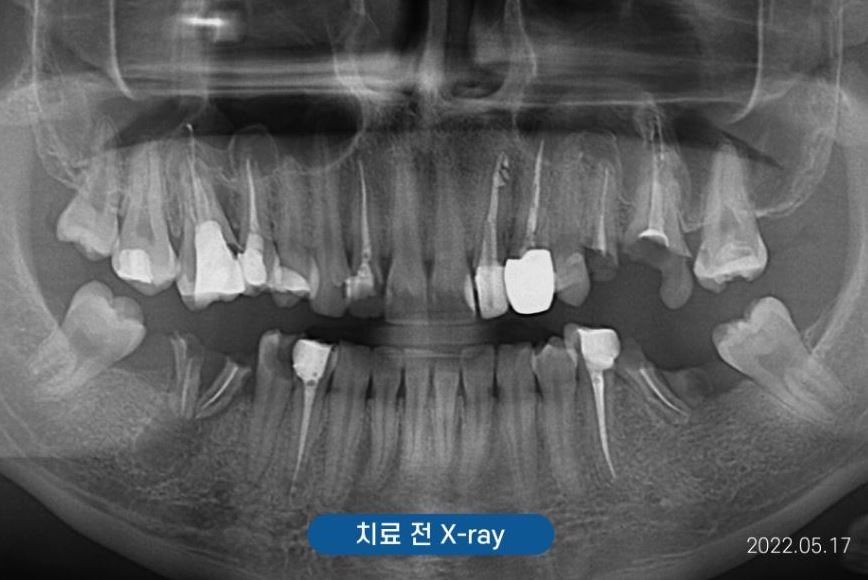

조금 더 정확한 검사를 하기 위해

X-ray(Panorama)와

구강포토를 촬영하였습니다.

아래쪽 양쪽 어금니와

위쪽 사진 기준 왼쪽 어금니가

많이 손상되어

치아머리가 더의 보이지 않았는데요.

식사의 어려움은 없으셨을까요?

않타깝게도 부러진 치아의 치질이

거의 없는 상태였기에

치아를 살릴 수 없어

양쪽 위 아래 어금니 임플란트로

계획을 세우게 되었습니다.